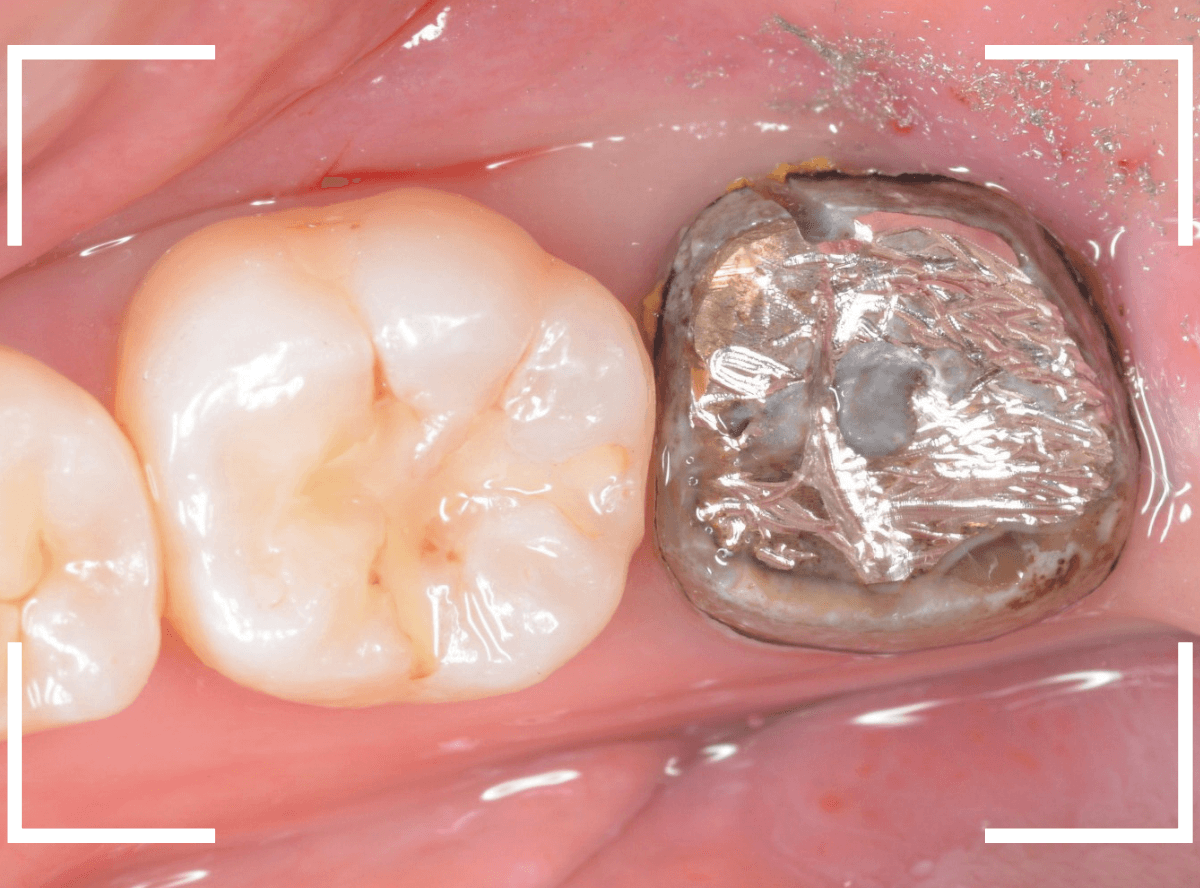

メタル・インレーとメタル・クラウンが入っていますね。

まずは、奥のメタル・クラウンを外します。

メタル・コアが入っていますが、こちらも慎重に外して、中を調べていきます。

レントゲン写真では問題なさそうでしたが、メタルコアを除去すると、中は真っ黒でした。

このように、コアの中で虫歯が進行している場合もありますので、さし歯をやり直す際は、出来る限りコアも外して調べるようにしています。